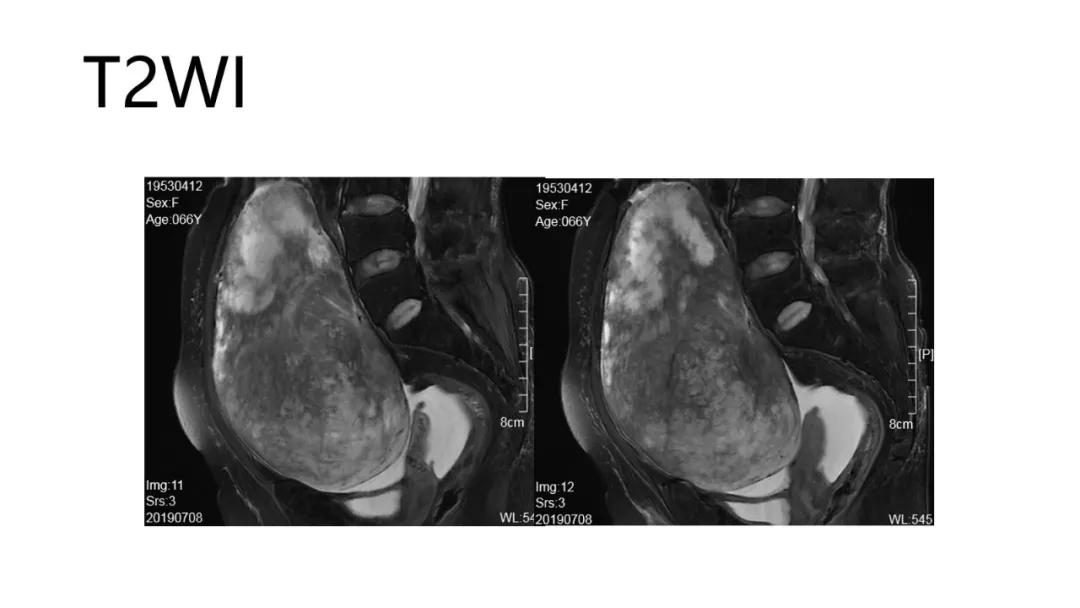

- 阴道不规则出血、闭经、量大:性索间质性肿瘤、子宫内膜样癌、透明细胞肿瘤

高雌激素症状:颗粒细胞瘤、卵泡膜细胞瘤(绝经期后出血及阴道不规则出血、性早熟、子宫内膜增生、乳房胀痛)